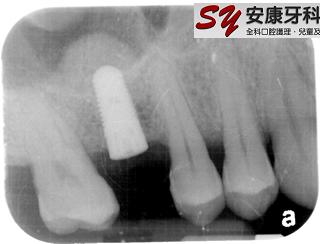

Sinus Lift: (Nov 2008)

There is usually limited bone height for upper back implant due to the presence of maxillary sinus.

Sinus Lift procedure was performed in this case by grafting extra bone into the maxillary sinus at the same time when placing the implant.